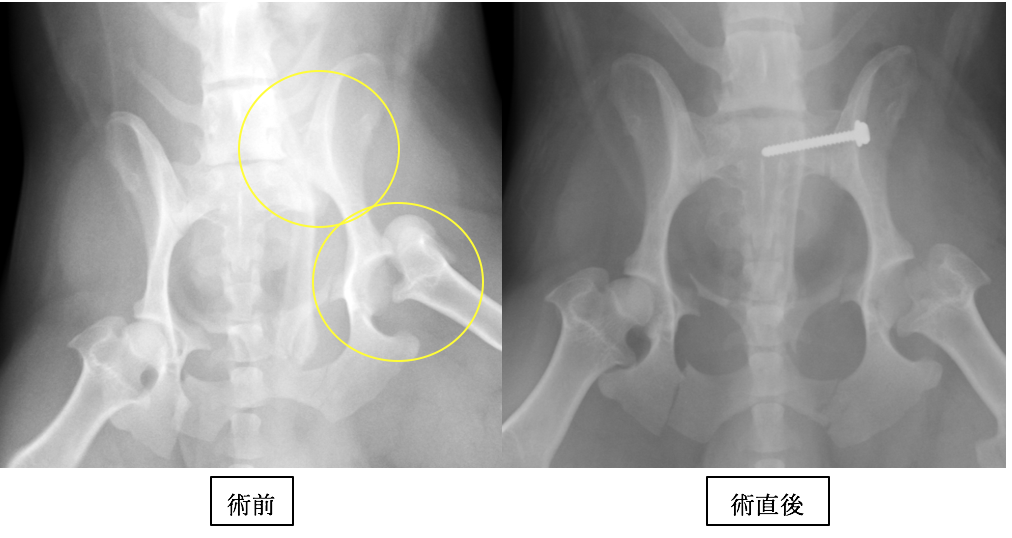

M・ダックスフンドです。痛みが強かったのですが、術後は骨折前と同じように活動できています。

数カ所折れていますが、重要なのは仙腸関節(上の◯)の脱臼と、股関節脱臼です。

仙腸関節はラグスクリュー法と呼ばれるスクリューによる固定を行い、股関節は大腿骨頭切除術と呼ばれる方法を行っています。